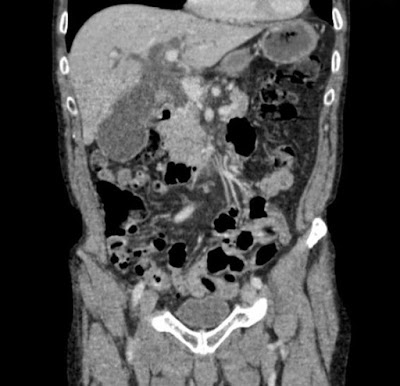

- Peritoneal carcinosis